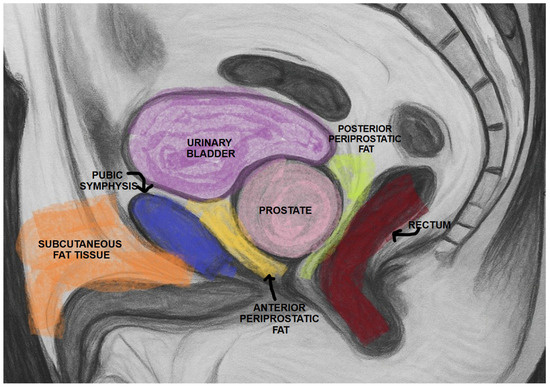

what is the best bony primary match structure of the prostate

the pubic symphysis

lies directly anterior to the prostate

what is the most important soft-tissue matching area on transverse CT for prostate patients?

prostate-rectal interface